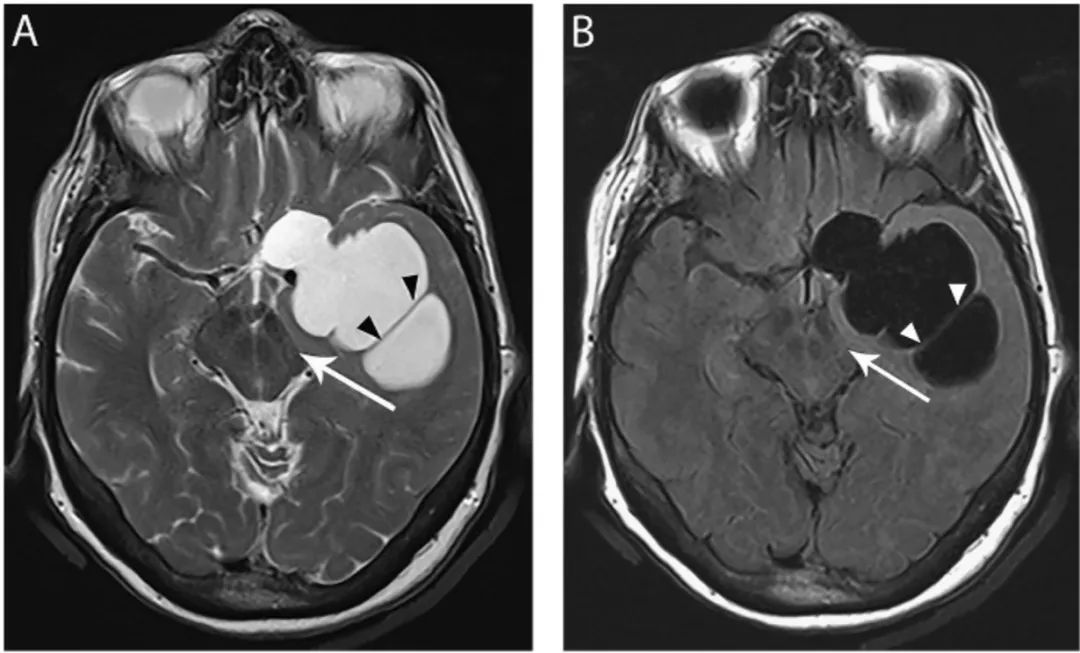

图5 大神经胶质的囊肿

轴位T2WI像(A)和FLAIR像(B)显示左侧前颞叶和后额叶有明显囊肿,等CSF信号,囊肿内可见分隔(黑箭头),左侧脑桥合并占位效应(长箭头)